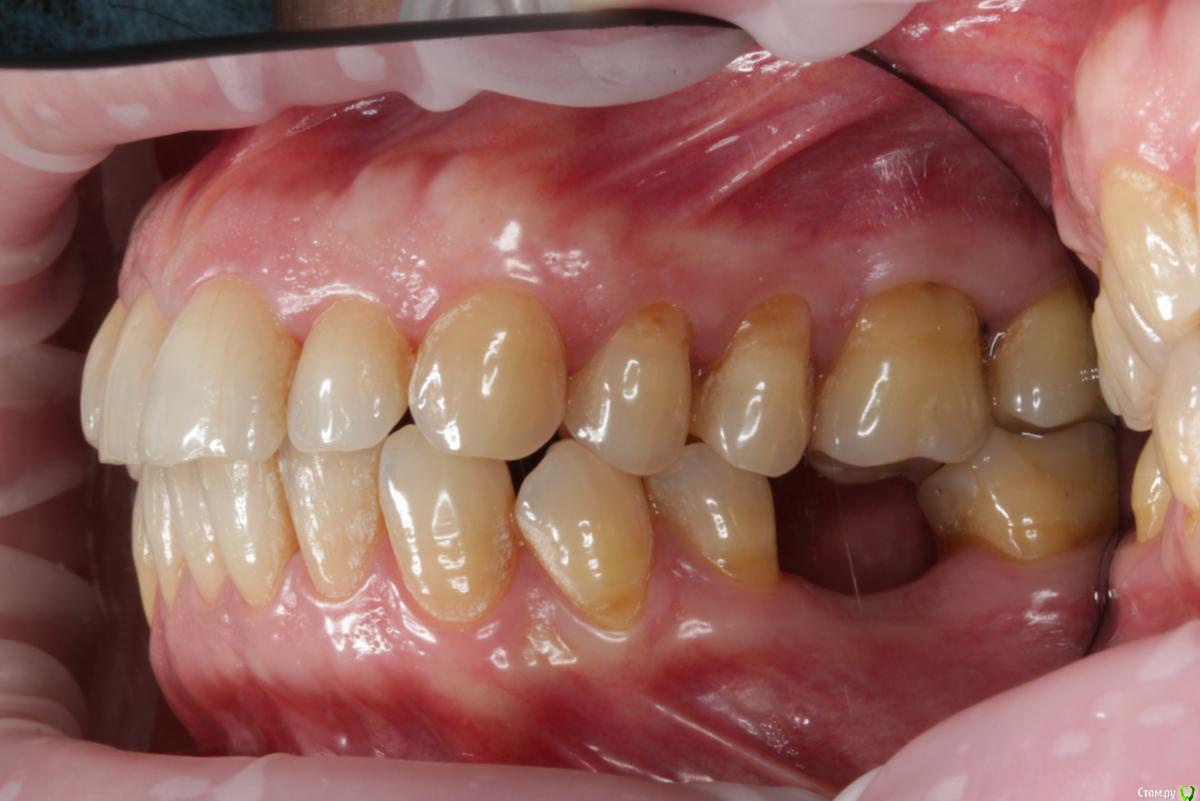

Dmitry DK Опубликовано 29 августа, 2019 Поделиться Опубликовано 29 августа, 2019 Добрый день всем! Случай достаточно заурядный, но возможно кому-то будет интересно. Результат - 2 года спустя 13 Ссылка на комментарий

Dmitry DK Опубликовано 18 сентября, 2019 Автор Поделиться Опубликовано 18 сентября, 2019 какая фиксация?Винтовая 1 Ссылка на комментарий